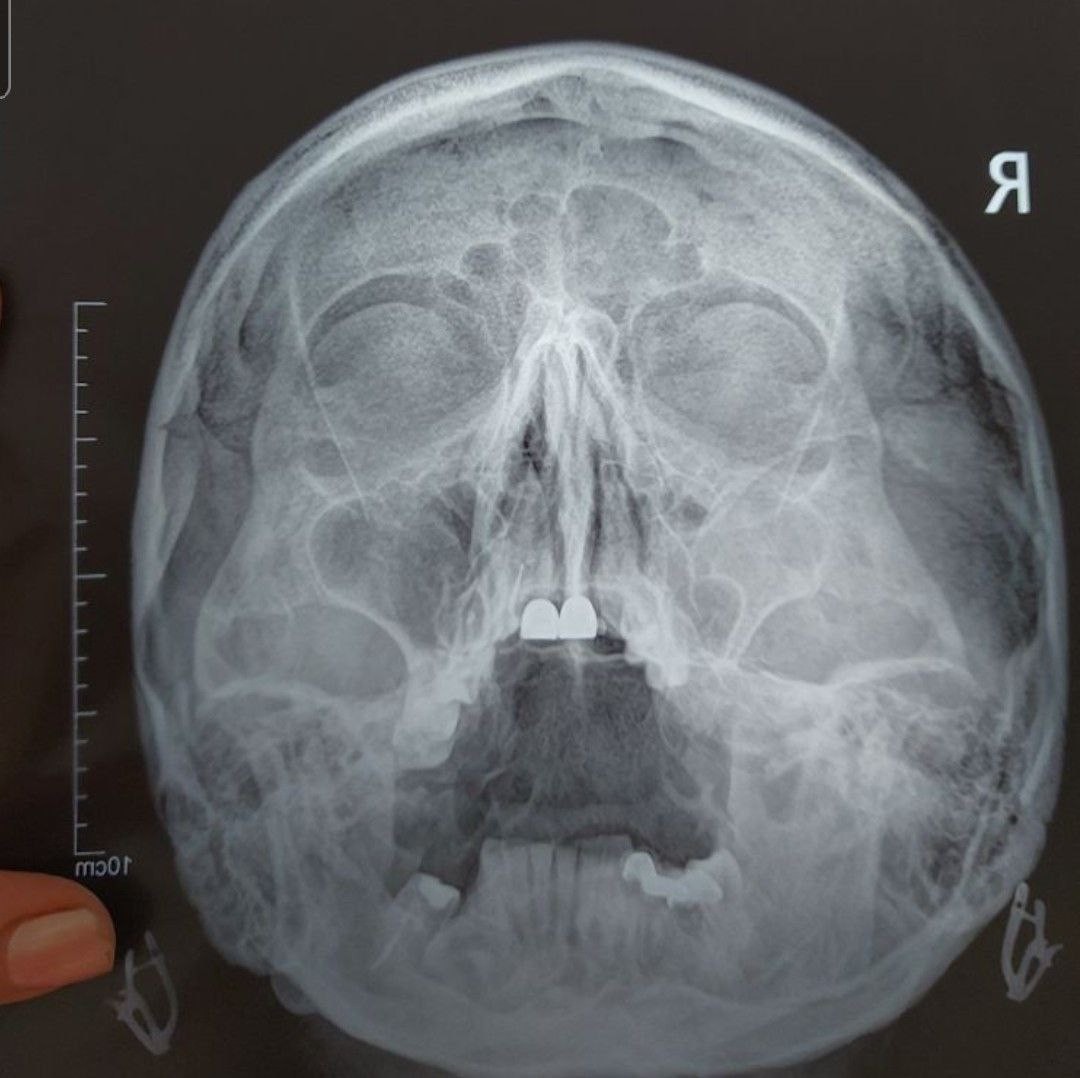

Тема: Исследование придаточных пазух носа

Пожалуйста проанализируйте снимок на наличие жидкости, кист, воспалений, отеков и т. д. в пазухах носа